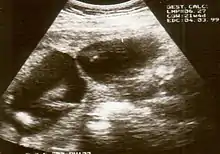

Diagnosis of constriction ring syndrome can be confirmed with an ultrasonography. The clinical manifestations can be extremely variable. It could be a single or multiple manifestation. This can be confirmed at the end of the first trimester or at the beginning of the second trimester.[13] However, not every patient will be diagnosed at that moment; most will be diagnosed at birth.

Individual strands are small and hard to see on ultrasound, so bands are detected indirectly because of the constrictions and swelling upon limbs or digits. Misdiagnosis is also common, so if there are any signs of amniotic bands, further detailed ultrasound tests should be done to assess the severity. 3D ultrasound and MRI can be used for more detailed and accurate diagnosis of bands and the resulting damage/danger to the fetus.